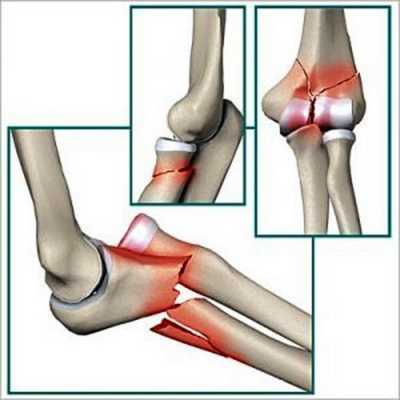

При таких травмах обычно повреждения локализованы в верхних третях локтевых костей. Происходит перелом локтевого отростка (переломо-вывихи Монтеджи).

Если произошло спровоцированное тягой трицепса смещение фрагмента, то проводится только оперативное лечение. Хирург восстанавливает хрящевые и костные ткани, а затем фиксирует отломки спицами и проволокой. Удаляют спицы примерно через полгода после оценки состояния локтя. А пластины извлекаются позже — через 1-2 года.

Благодаря близкому расположению локтевого отростка к коже операция длится недолго и не представляет сложности. Но есть и исключения — многооскольчатые переломы с повреждениями венечных отростков. Они закрепляются специальными хирургическими металлическими конструкциями.